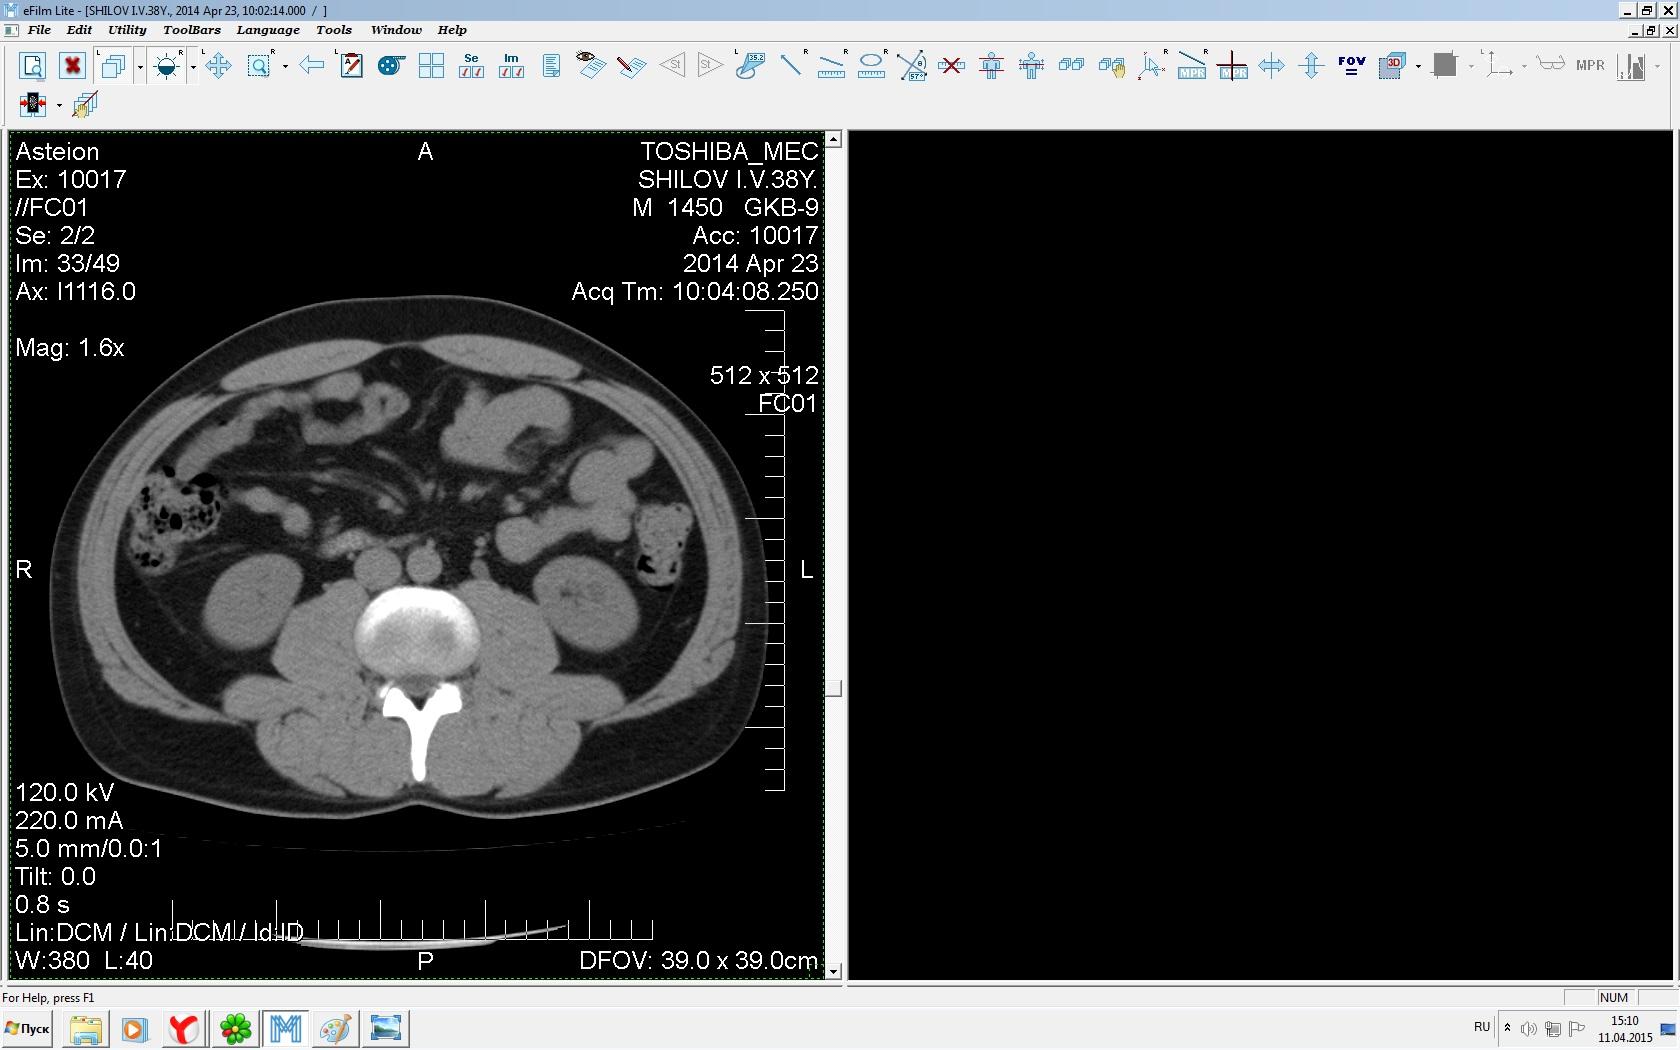

Здравствуйте. У меня киста левой почки. Из заключения: левая почка увеличена, деформирована за счёт наличия в среднем сегменте округлого жидкостного +6, +15 HU образования 66х53 мм, деформирует, поддавливает чаше-лоханочную систему. Сосудистые ножки структурные. В урологии мне сперва предложили лапароскопию, когда я лёг на операцию - изменили на полостную в связи со сложностью. Потом сказали что шансов вырезать кисту без почки практически нет. Даже если кисту удалить чудесным способом, то почка всё равно сложится и не будет работать. В итоге операцию отменили. Скажите, пожалуйста, есть ли современный метод удалить кисту и сохранить почку в моём случае? Томография почки в приложениях. Заранее благодарю.

Эту кисту можно просто пропунктировать, аспирировать и склерозировать - под местной анестезией. Ничего сверхестетственного не определяется по данным КТ. Можете написать мне на почту. aristova-tatyana@mail.ru